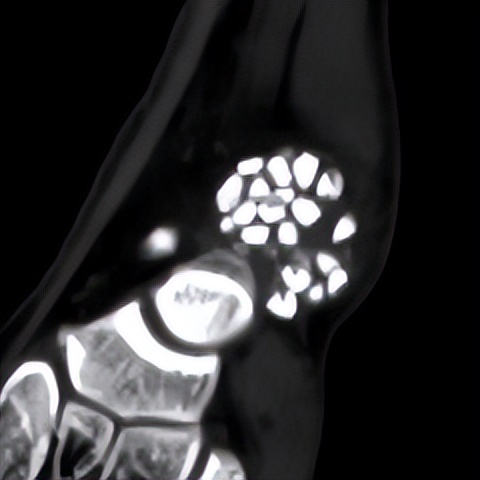

何河北制定了详细的手术方案,为患者开展踝关节镜下滑膜软骨瘤取出术+距腓前韧带重建术。他从患者踝关节中取出32颗“珍珠”(关节游离体),然后进行踝关节外侧韧带重建。

▲术中取出31颗滑膜软骨瘤。

▲术后CT显示滑膜软骨瘤完全取出,韧带重建良好。